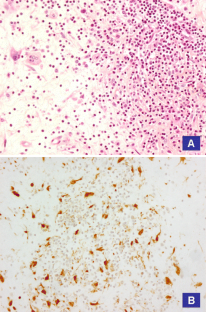

Fig. 1

Fig. 2

Fig. 3

Fig. 4

Fig. 5

Fig. 6

Fig. 7

Fig. 8

Fig. 9

Fig. 10

Fig. 11

Fig. 12

Fig. 13

Fig. 14

Fig. 15

Fig. 16

Fig. 17